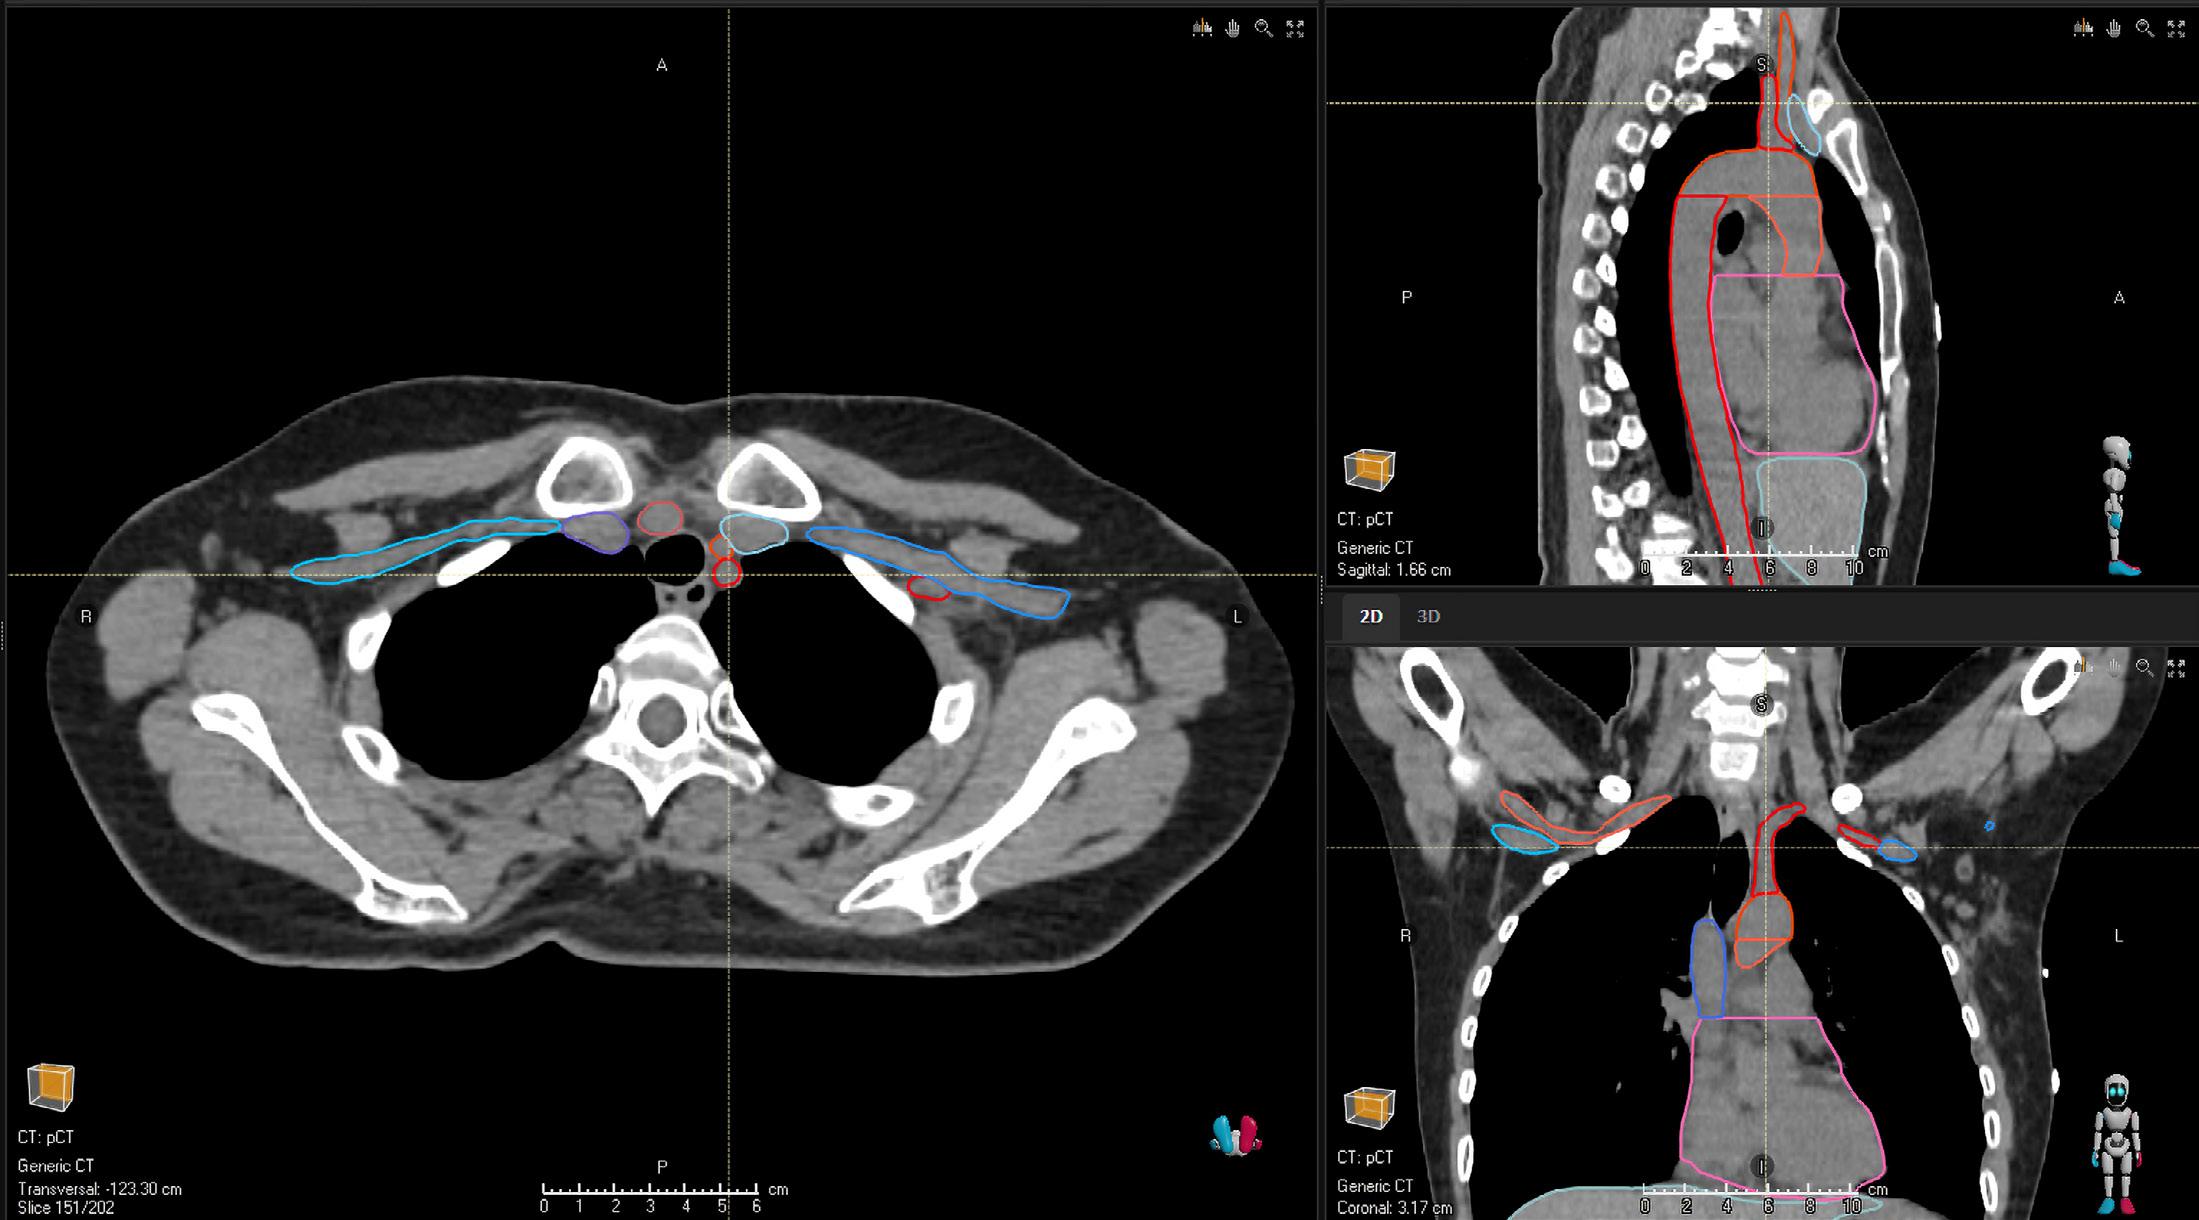

BREAST CT

STRUCTURES

Breast_L

Breast_R

LN_Ax_L1_L IMPROVED

LN_Ax_L1_R IMPROVED

LN_Ax_L2_L IMPROVED

LN_Ax_L2_R IMPROVED

LN_Ax_L3_L IMPROVED

LN_Ax_L3_R IMPROVED

LN_Ax_Pectoral_L IMPROVED

LN_Ax_Pectoral_R IMPROVED

LN_IMN_L

LN_IMN_R

LN_L4_L IMPROVED

LN_L4_R IMPROVED

HEART SUBSTRUCTURES

A_Aorta_Asc_Prox NEW

A_Aorta_Root NEW

A_LAD

A_Pulmonary NEW

Atrium_L NEW

Atrium_R NEW

V_Pulmonary NEW

V_Venacava_S_Prox NEW

Ventricle_L NEW

Ventricle_R NEW